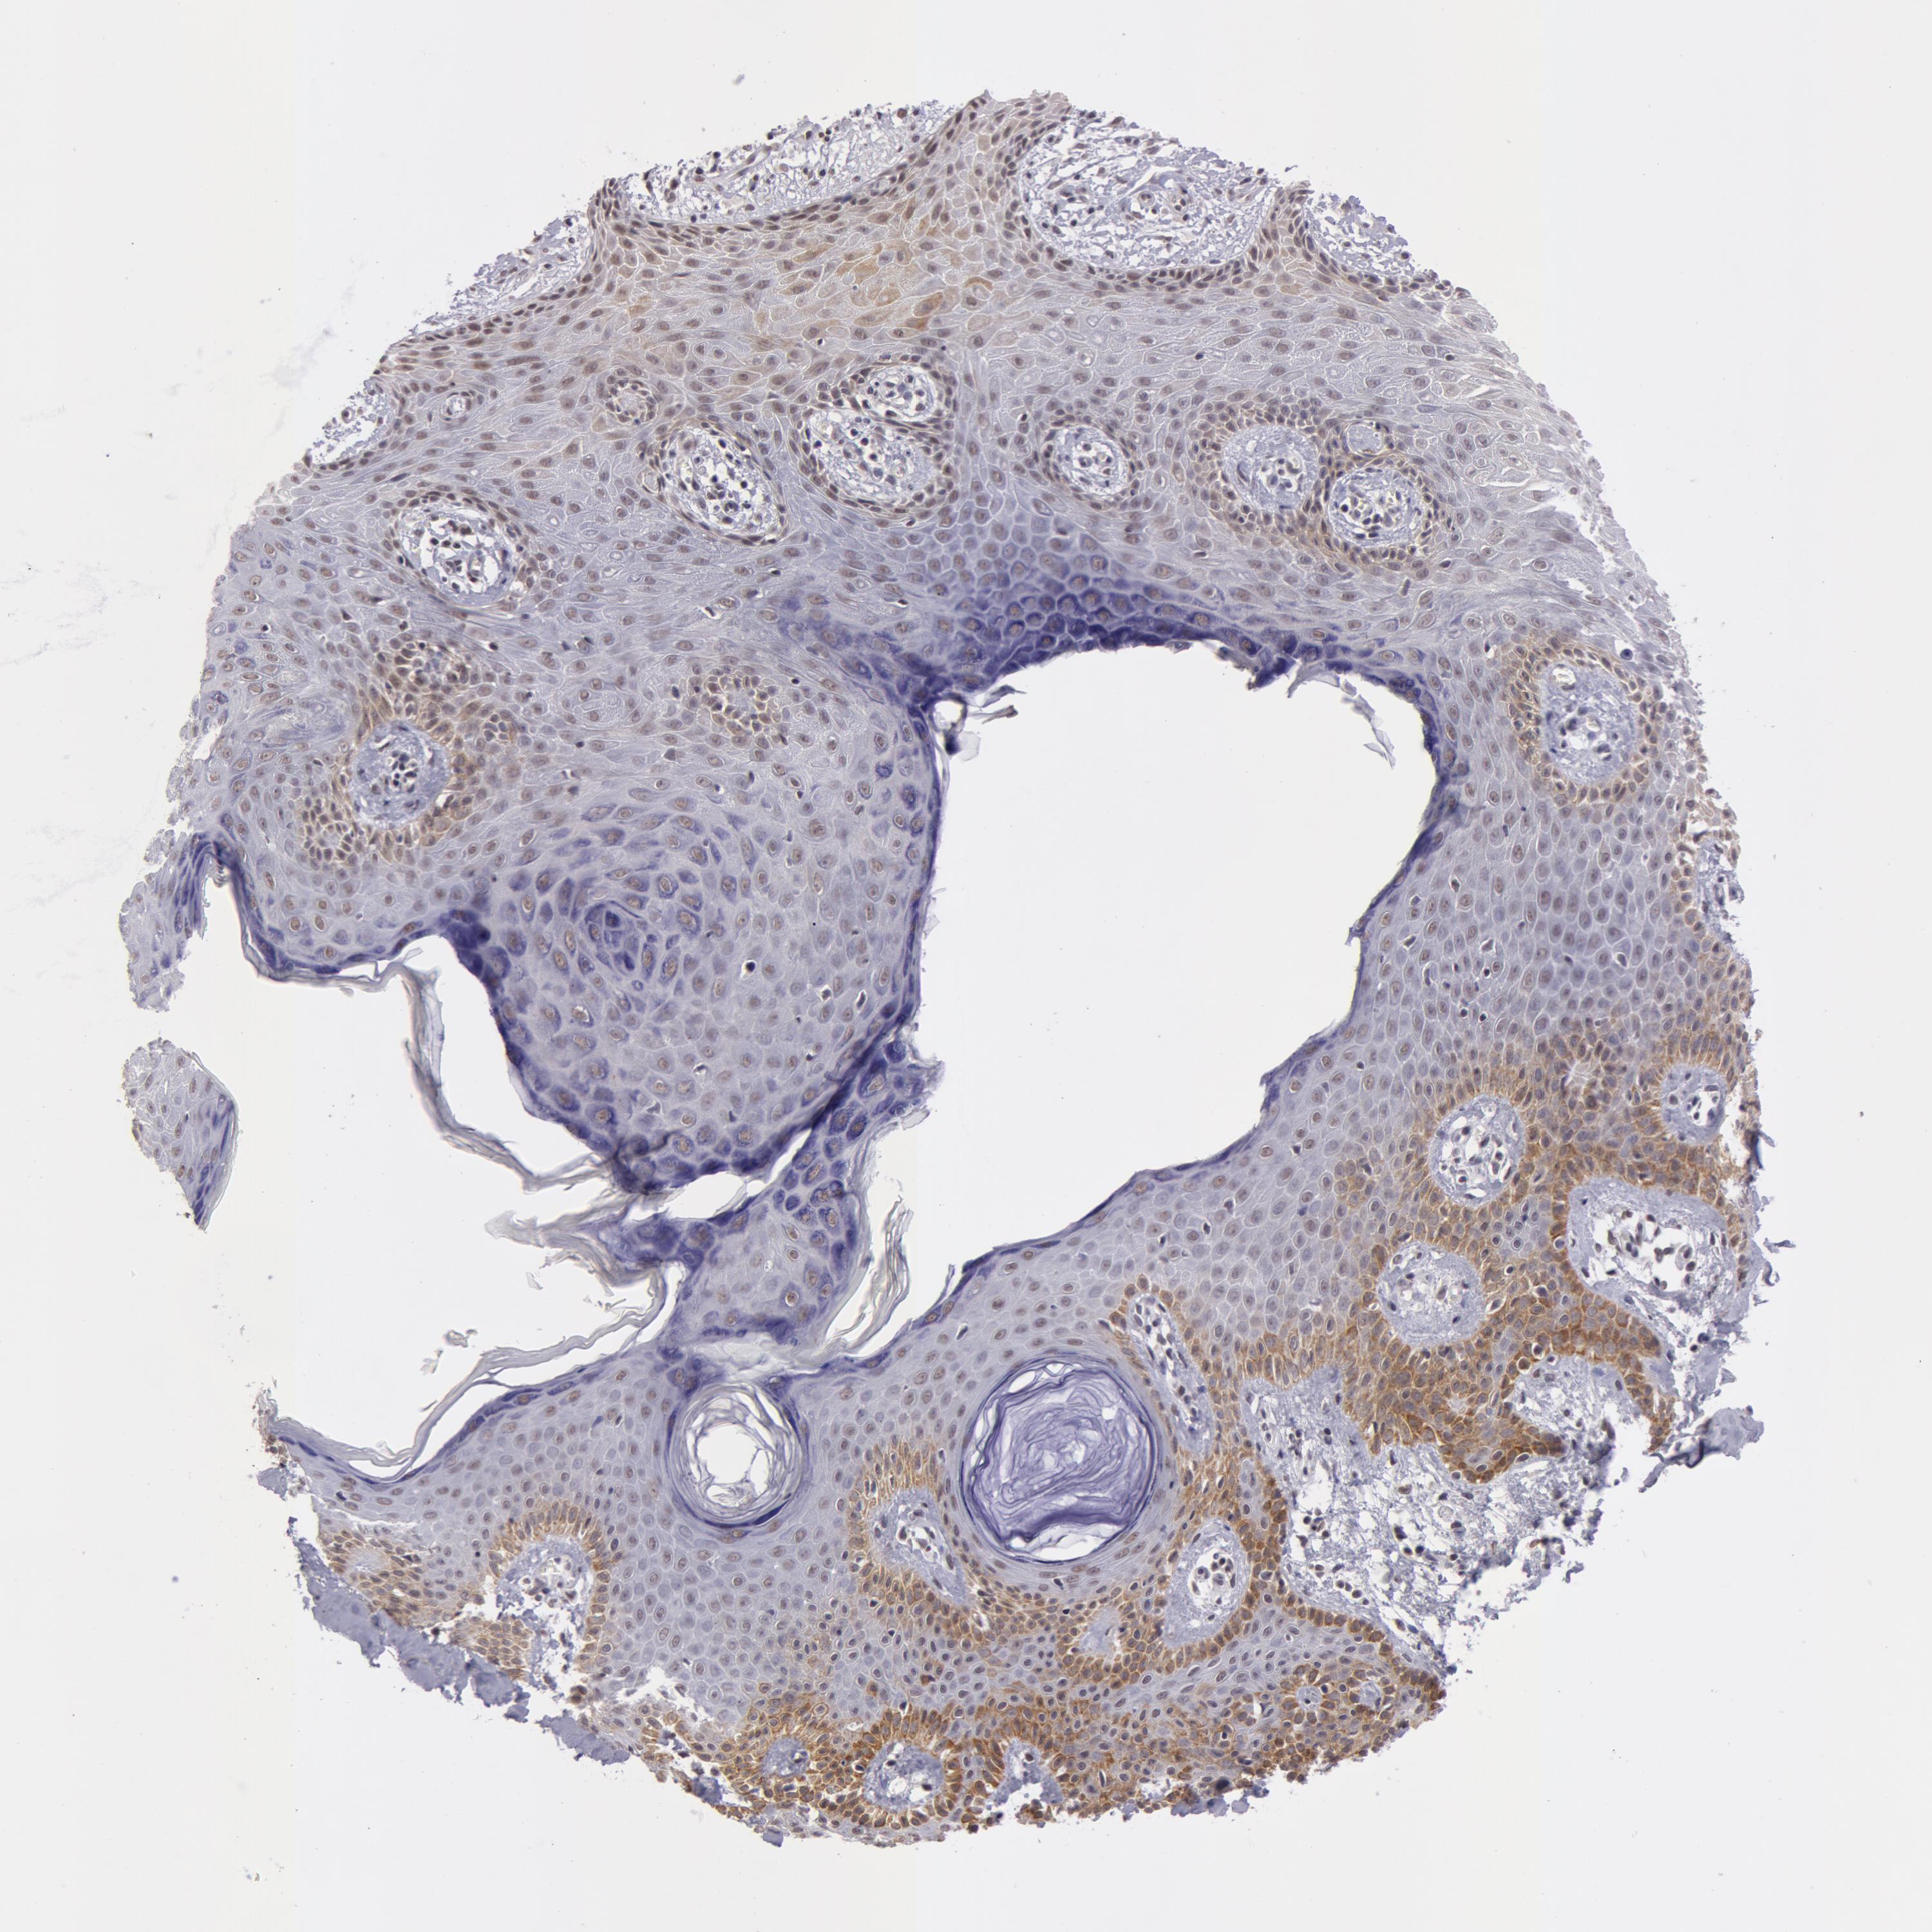

SKIN CANCER - Protein expressioni

A mouse-over function shows sample information and annotation data. Click on an image to view it in a full screen mode. Samples can be filtered based on level of antibody staining by selecting one or several of the following categories: high, medium, low and not detected. The assay and annotation is described here.

Antibody stainingi

Antibody staining in the annotated cell types in the current human tissue is reported as not detected, low, medium, or high, based on conventional immunohistochemistry profiling in selected tissues. This score is based on the combination of the staining intensity and fraction of stained cells.

Each image is clickable and will lead to virtual microscopy that enables deeper exploration of all samples and also displays staining intensity scores, fraction scores and subcellular localization as well as patient and tissue information for each sample.

Antibody HPA001460

Staining

High

Medium

Low

Not detected

Intensity

Strong

Moderate

Weak

Negative

Quantity

>75%

75%-25%

<25%

None

Location

Nuclear

Cytoplasmic/membranous

Cytoplasmic/membranous,nuclear

Squamous cell carcinoma, NOS

Basal cell carcinoma